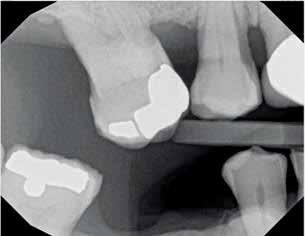

The inclusion criteria were patients within 20 to 40 years with unrestorable bilateral teeth with a harmonious gingival contour, having a thick

gingival phenotype, and at least 4 mm of bone apical to the root apex and 2mm labial plate of bone of the unrestorable tooth to be extracted and absence of any periapical radiolucency (Fig 1). 12 Any patient su ering from medical disorders interfering with osseointegration or soft tissue healing, active oral infections or periodontal disease, presence of dehiscence or fenestration defects related to the tooth to be extracted, poor oral hygiene, and heavy smokers was excluded from the study 13

Post preparation of the root canal space must not remove additional dentin, as this contributes to a reduced fracture toughness. (Fig. 1)

Figure 1 Especially in ovoid canals (which are the norm) post preparation needlessly remove dentin and result in weakening the remaining tooth structure, leaving lateral gutta percha which compromises bonding/cementation.

Figure 1 Especially in ovoid canals (which are the norm) post preparation can needlessly remove dentin and result in weakening the remaining tooth structure, while leaving lateral gutta percha which compromises bonding/cementation.

Figure 1 — Especially in ovoid canals (which are the norm) post preparation can needlessly remove dentin and result in weakening the remaining tooth structure, while leaving lateral gutta percha which compromises bonding/cementation.